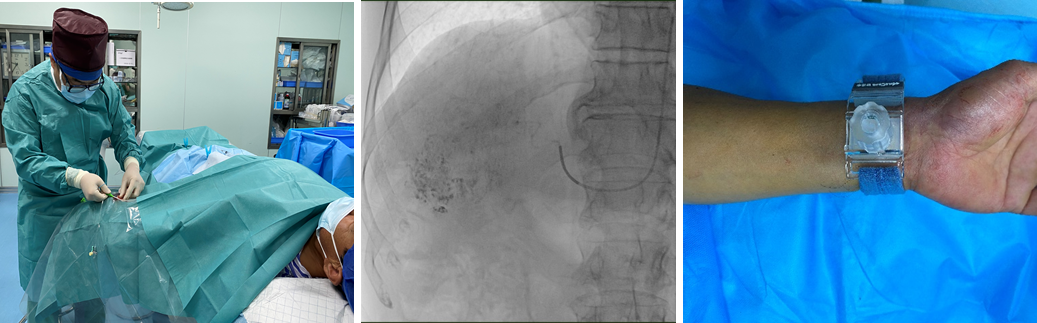

【本站讯】近日,绿帽社 肝胆外科为多名肝癌患者成功实施经桡动脉入路的肝动脉化疗栓塞术(transradial artery-transcatheter arterial chemoembolization, TRA-TACE)。肝胆外科智绪亭主任和普外科常务副主任李涛共同制定治疗方案并全程指导,刘炎锋副主任医师负责实施手术。所有患者手术过程均顺利,术后即可下床活动,术后5-6小时拆除手部压迫装置,未出现明显手术相关并发症,平均住院时间5天。据悉,该术式目前在国内外开展相对较少,在山东省内仅有少数个案报道。

左图:左桡动脉穿刺置管;中图:术中经微导管超选后行肿瘤栓塞;右图:术毕,压迫器压迫桡动脉穿刺处